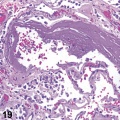

获得性囊性肾病相关性肾细胞癌临床病理学特征概述

1、概述获得性囊性肾病(acquired cystic kidney disease,ACKD)在1977年由Dunnill等首次报道,定义为发生于肾衰竭终末期或透析患者一类肾脏慢性进行性多发囊肿性疾病。目...